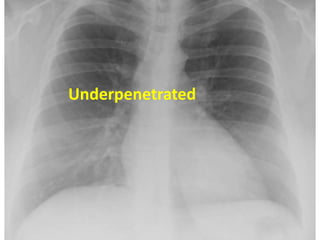

Exposure : You must barely see the thoracic vertebrae

behind the heart

Underpenetrated

Under-penetrated